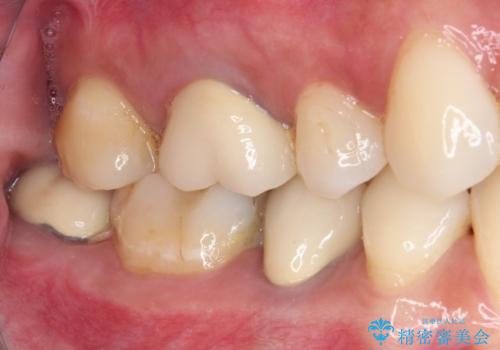

ドイツやベルギーなどで治療を受けた奥歯2本が食事の度にしみているとのことで、レントゲン検査や視診を行ったところ、補綴物や修復物の適合が悪く、それが原因であると考えられました。

いずれの歯も症状に異常なく、オールセラミッククラウンにて補綴治療を行うこととしました。

歯とクラウンの適合が良くなることで、食事の度にしみるという症状はなくなり、歯間部にものが挟まって不快な思いをすることもなくなりました。